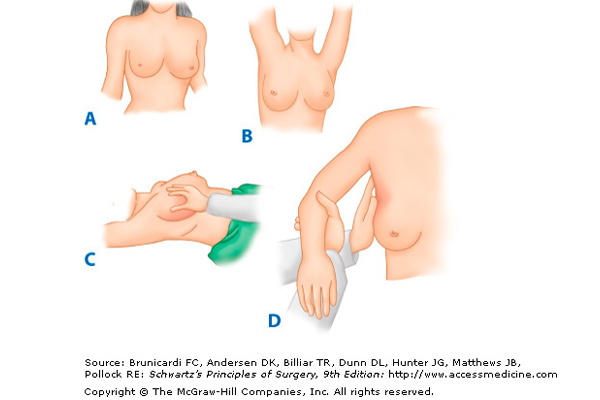

Meme de kanser gelişimi genelde önceleri hasta fark etmez. Bir hücrede değişim başladığında o hücrenin 2’ye bölünmesi (dupling time) en az 50-100 gündür. Bu odağın görülebilir olması için geçen süre 1 kaç yılı bulur. Meme kanserinde boyut çok önemlidir. 1 cm’nin altındaki kanserlerin tedavisi kolay, genellikle meme koruyucu tarzında ve özellikle kemoterapi almayacak seviyededir. Onun için tarama ve yıllık kontroller son derece önemlidir. Meme muayenesi her ay birey tarafından, adet gören bireylerde adet sonraki haftada, menopoz dönemindeki bireyler ise saptadıkları bir tarihte aylık kendi kontrollerini yapmaları gerekir.

Meme kanserinde 20 yaşından sonra 41 yaşına kadar her kadın periodik olarak her yıl kontrol edilmelidir ve meme us ile kontrol edilip memede kitle olup olmadığı bu kitlenin kistik veya solit olup olmadığı solit kitleninde maliğn özellik taşıyıp taşımadığı saptanmalı, maliğn özellik taşıyorsa biopsi yapılmalıdır. 41yaşından büyük hastalarda ise meme us’na a mamografi ilave edilmelidir. Mamografi yapılamayan hastalarda meme MR tanıda yardımcı olmakta maliğn şüpheli vakalarda biopsi uygulanmaktadır.